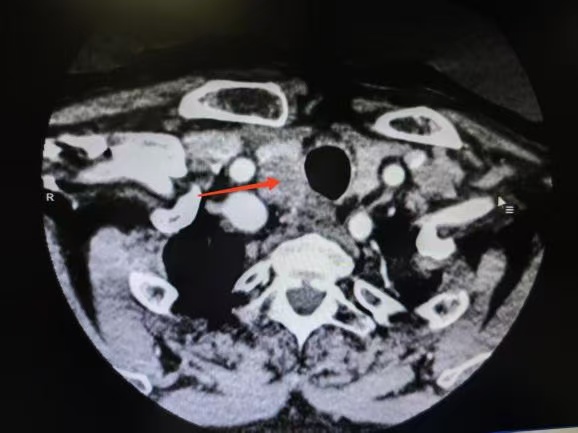

CT箭頭所示:右側(cè)甲狀腺腫瘤

荊楚網(wǎng)(湖北日報網(wǎng))訊(通訊員 楊青青 沈浩元 )近日,孝感市中心醫(yī)院甲狀腺乳腺外科成功為一名67歲男性患者實施了高難度甲狀腺癌根治手術(shù)。該患者因頸部突發(fā)硬塊4天就診,經(jīng)檢查確診為雙側(cè)甲狀腺乳頭狀癌伴右頸側(cè)區(qū)多發(fā)淋巴結(jié)轉(zhuǎn)移,術(shù)中進一步發(fā)現(xiàn)腫瘤已侵犯包繞喉返神經(jīng),側(cè)區(qū)轉(zhuǎn)移淋巴結(jié)亦侵犯頸內(nèi)靜脈,病情復雜且兇險。